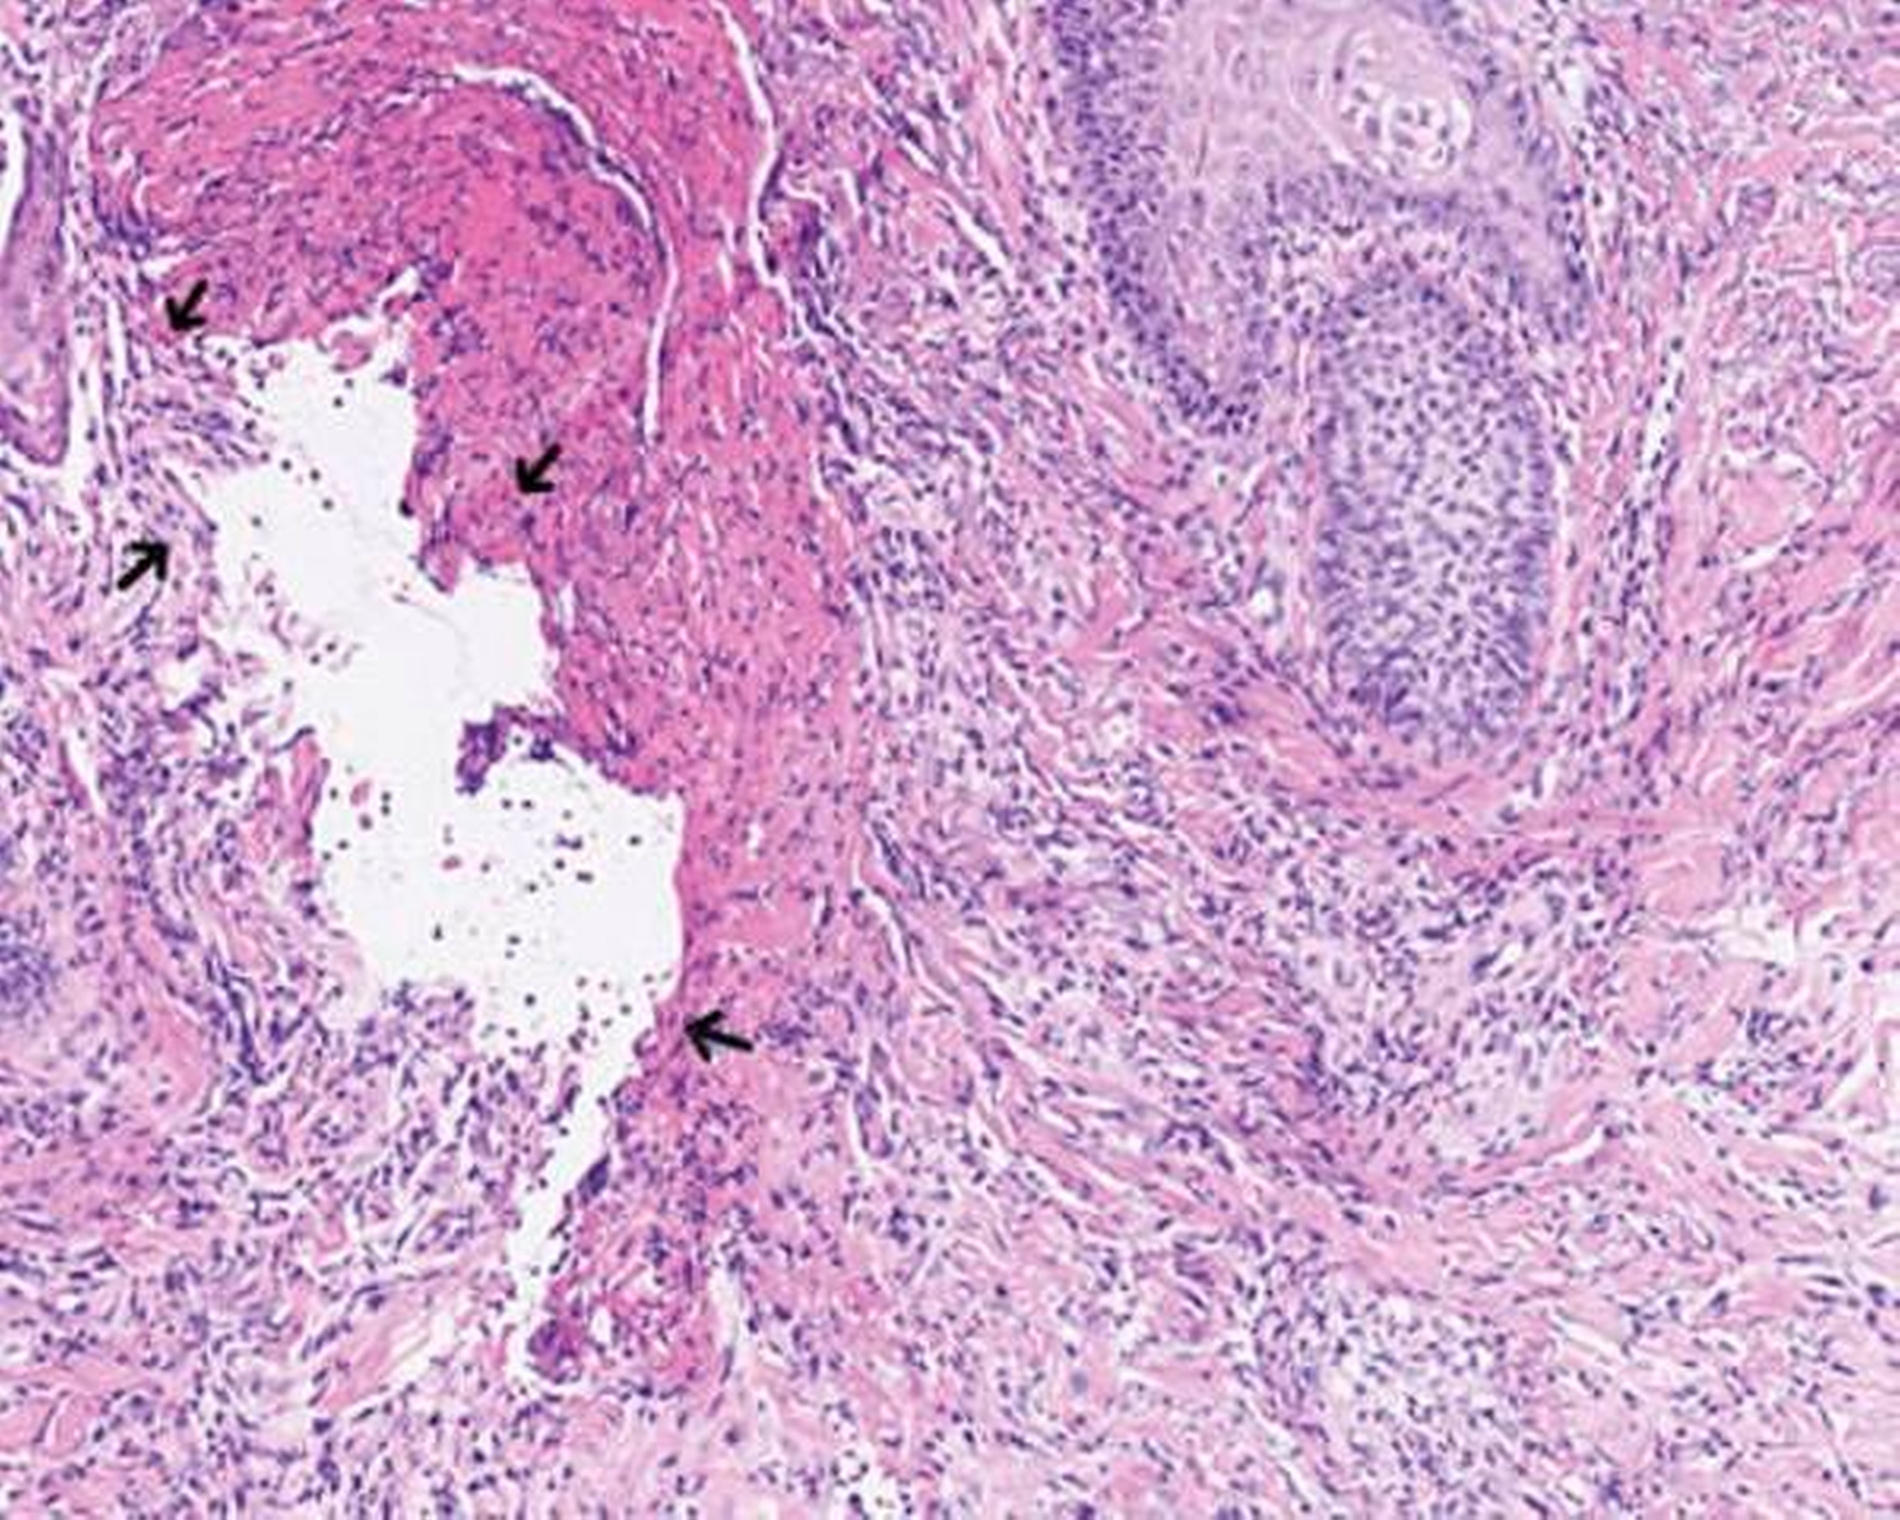

Mikroskopisch zeigten sich eine floride Ulzeration mit Fibrinexsudation und perivaskulären, entzündlichen Infiltraten mit neutrophilen Granulozyten sowie reaktive Veränderungen der Epidermis (Abbildungen 2 und 3). Auch bei einem erneuten Abstrich konnten keine Bakterien nachgewiesen werden.

Im Spätstadium zeigt sich histologisch eine Infiltration mit neutrophilen Granulozyten sowie Hämorrhagien [Su et al., 1986; Callen et al., 1998].